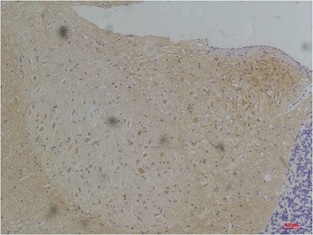

Immunohistochemical analysis of paraffin-embedded Rat BrainTissue using KV1.1 Potassium Channel (BE3524)Rabbit pAb diluted at 1:200

Immunohistochemical analysis of paraffin-embedded Mouse BrainTissue using KV1.1 Potassium Channel (BE3524) Rabbit pAb diluted at 1:200